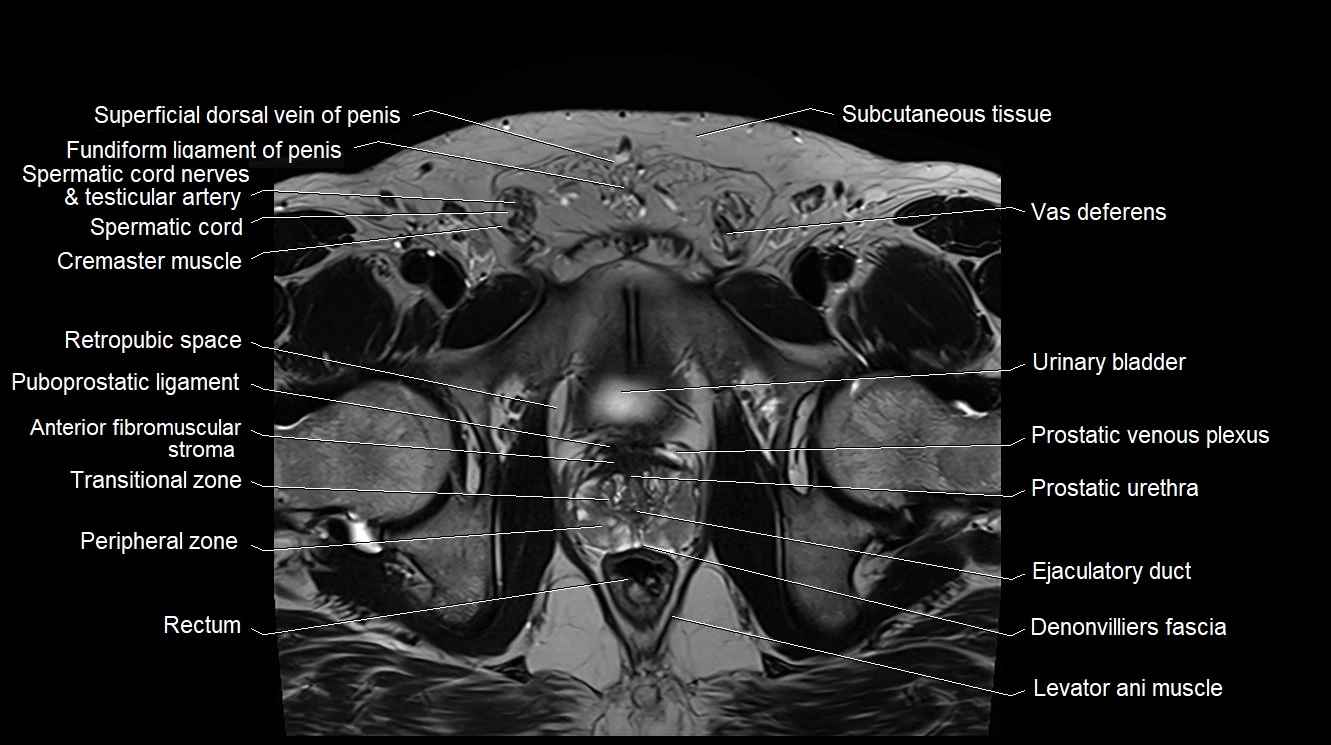

MRI image